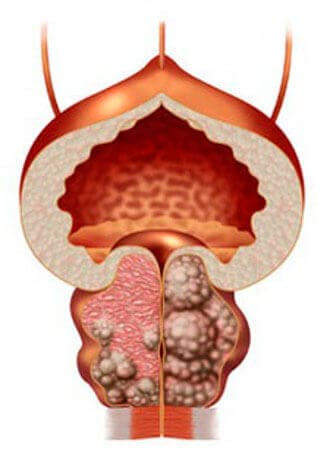

التهاب البروستاتا العادي

تضخم البروستاتا الحميد

إذا لم تعالج التهاب البروستاتا ، فإنه يتطور بسرعة كبيرة ويؤدي غالبا إلى ورم غدي في البروستاتا ("موت الذكورة")

تقريبا يمكننا أن نفهم الرجال المصابين بهذا المرض ، لا سيما بالنظر إلى مستوى الطب في البلاد في معظم الحالات ، بعد تشخيص التهاب البروستاتا ، تصبح زيارة طبيب المسالك البولية سنويًا بشكل حاد. يخمد الأطباء الأعراض الحادة بالأدوية التي ينصح بها الصيادلة ، ولكن مع كل قشعريرة أو عدم امتثال ، يقوم التهاب بمهاجمة البروستاتا مرة أخرى